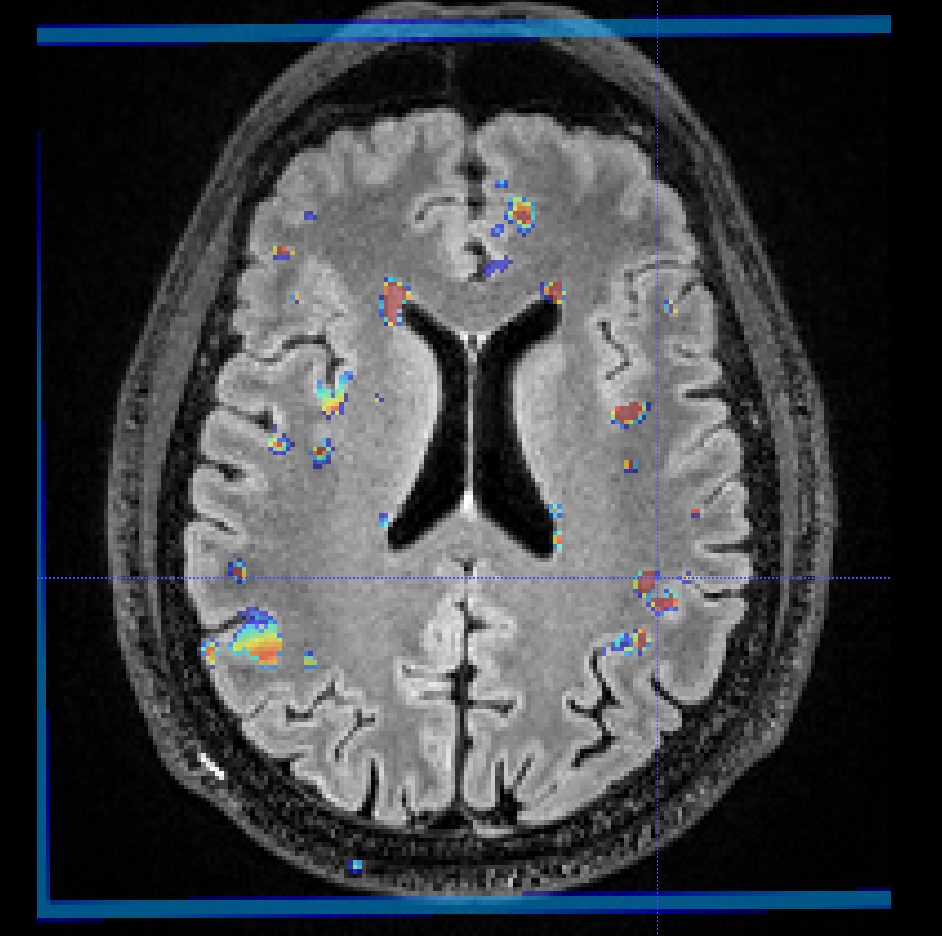

looked at results and saw:

maybe multiply the output probabilities with brain mask after mapping back to original space?

what do you think? I guess the last step could cause some loss of "real" WMH but it would remove some of the spurious signal in the cortex. maybe it would be better to just set all CSF ( and maybe cortex) to zero?